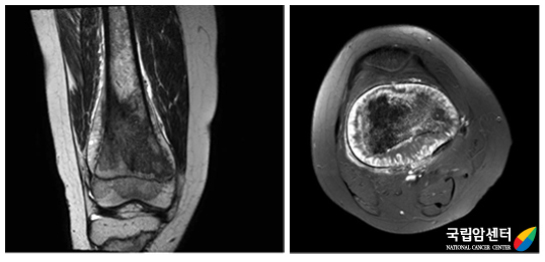

연부조직종양을 판단하는 데 탁월한 검사입니다. 특히 종양의 병기(stage)를 결정하는 데 필수적인 검사로 종양과 주위 조직 특히, 혈관 및 신경과의 상관관계를 파악하는 데 중요한 검사입니다. 또한 종양에 대한 항암화학요법 전후에 영상을 비교하여 치료 효과 판정에 이용하기도 합니다. MR 분광기(spectroscopy)의 사용으로 종양실질의 구성 성분을 예측할 수 있어 진단에 도움을 줍니다.

[ 자기공명영상(MRI) ]

[ 왼쪽 무릎관절 주위에 발생된 활막육종 환자의 사진 ]